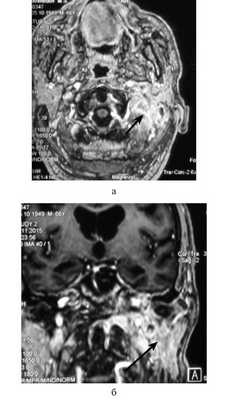

Всем пациентам выполняли КТ и МРТ височных костей и основания черепа с контрастированием. В 4 случаях отмечалось распространение воспалительного процесса на затылочную кость. КТ височных костей позволяло определить участки костной деструкции, в то время как МРТ использовали для идентификации точных границ патологических изменений, вовлеченности в процесс мышц и костей основания черепа, мозговых оболочек, интракраниального распространения воспалительного процесса (см. рисунок).

МРТ основания черепа больного Н. Диагноз: злокачественный наружный отит. а — аксиальная проекция; б — коронарная проекция. Под каменистой частью левой височной кости определяется воспалительный инфильтрат, накапливающий контрастный препарат (стрелка).